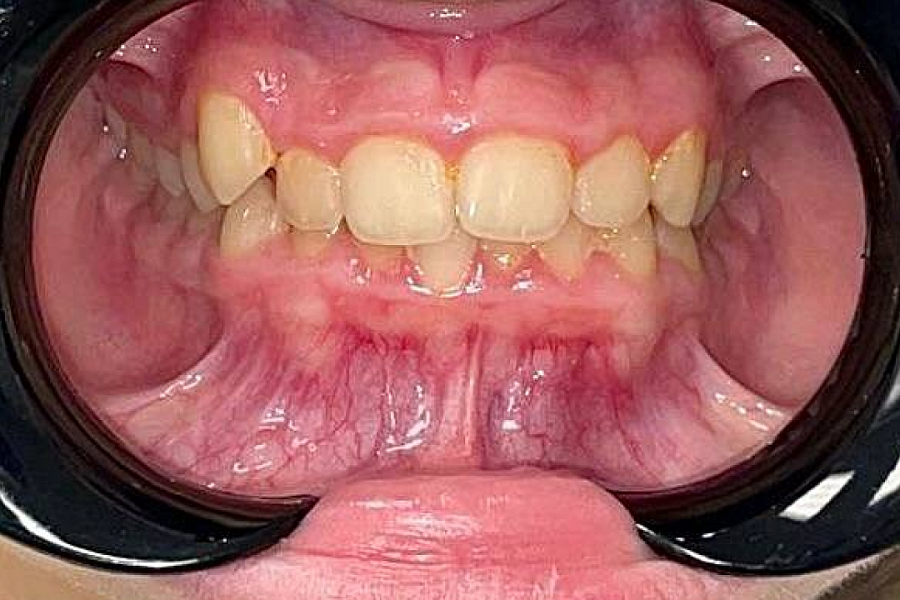

- Провели работу на функциональном аппарате, увеличивающем объем костной ткани верхней челюсти

- На нижнюю челюсть поставили расширяющую пластинку.

Изменения отлично видны на фото: положение зубов значительно изменилось. Зубки теперь растут ровными рядами.